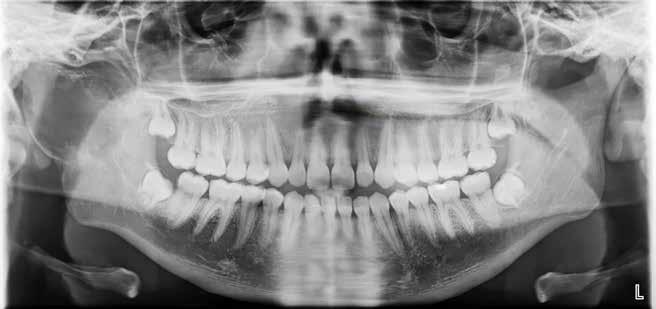

Patienttilfælde 1 (Fig. 1) er en 37-årig kvinde, henvist efter succesfuld behandling af stadie 3-parodontitis. Der er nu sundt

Der ses anterior trangstilling i begge kæber og overerupterede 1+1 og 2,1-1,2, hvilket resulterer i dybt bid med 2- tæt på ganepåbidning. Der er normale sidetandsrelationer, men der ses 5 mm horisontalt overbid (HOB) og 7 mm vertikalt

overbid (VOB). Papillen mellem 1+1 er betydeligt reduceret pga. fæstetab, og de mesialt kippede 1+1 har resulteret i en ”dark triangle”. Den facioorale funktion er for nuværende i.a. Panoramarøntgen (Fig. 1, I) viser marginalt knogletab i begge kæber og fravær af 8,7+7,8 og 8,7-8.